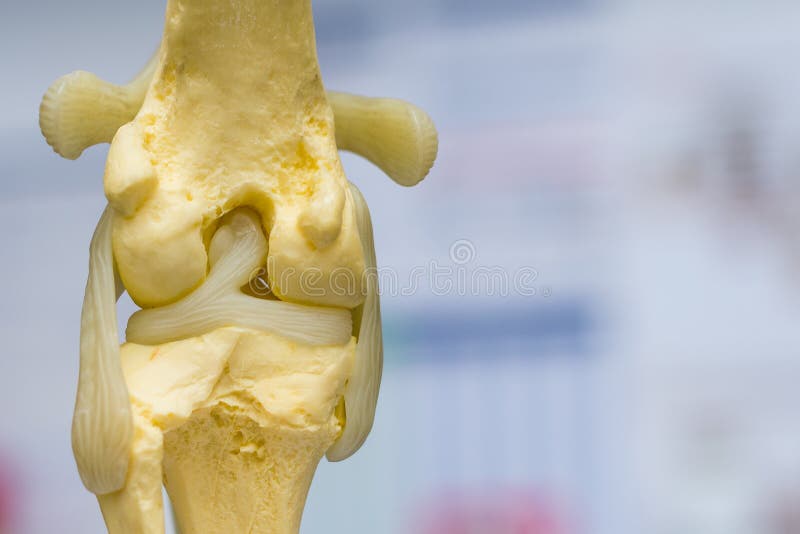

From www.dreamstime.com

Dog Knee Joint Mold Back View, Meniscus and Cruciate Ligament Stock Dog Knee Meniscus Tear Meniscal injuries on their own are uncommon in dogs, but the medial meniscus is very prone to tearing when the cranial cruciate ligament is ruptured. Limping is often the first sign of a cruciate problem. A dog’s knee, also referred to as a stifle, is a complex structure consisting of: The meniscus can also degenerate over time. Dogs and cats. Dog Knee Meniscus Tear.